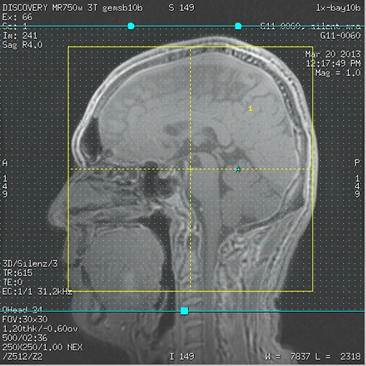

Figure 2. Example of IR saturation band placement

- Placement of the IR band edges is critical in order to avoid signal suppression in the final images.